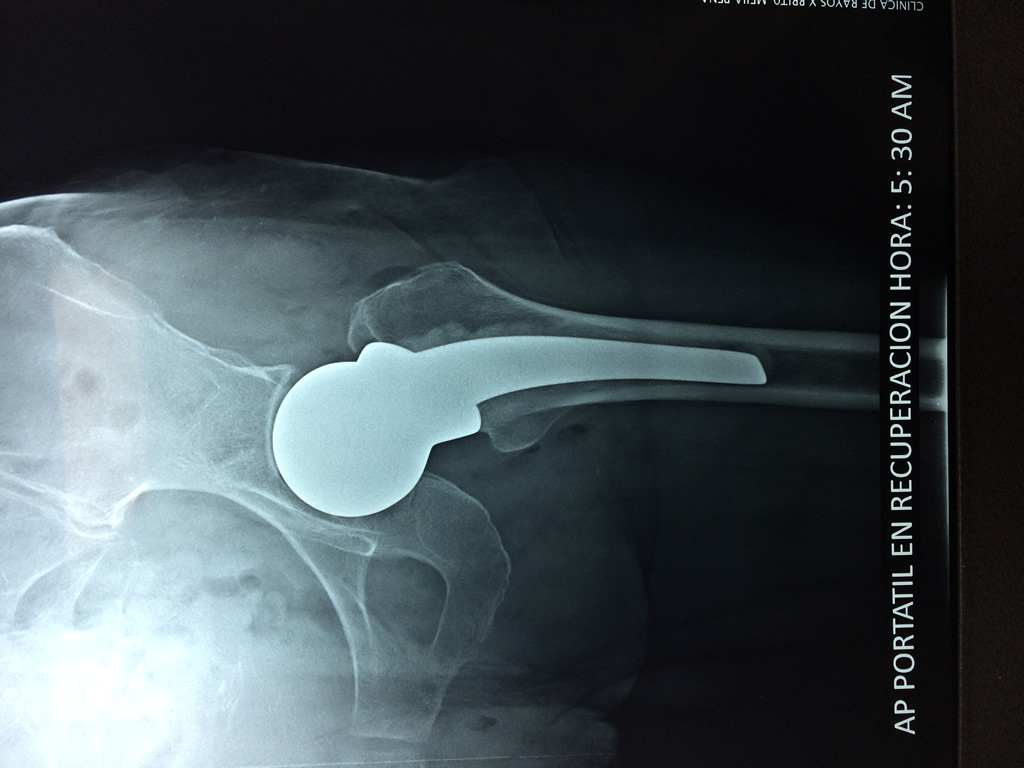

Fémur - Cadera

La cirugía de fractura de cadera se realiza para reparar una ruptura en la parte superior del hueso del muslo. Este hueso se denomina fémur.

Es parte de la articulación coxofemoral. Si una fractura de cadera no recibe tratamiento, es posible que deba permanecer en una silla o en la cama.

A menudo se recomienda la cirugía para reparar la fractura debido a dichos riesgos.